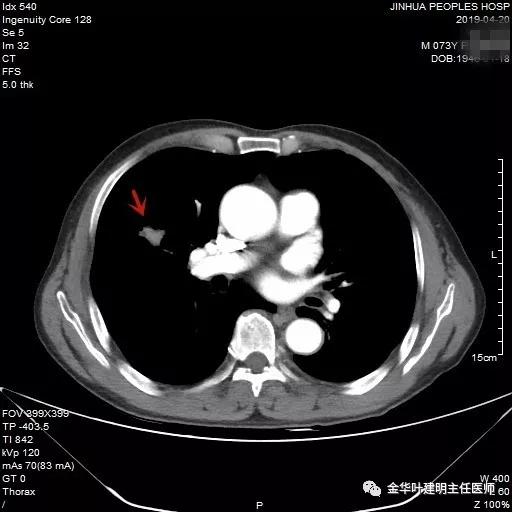

吴某不同意肺穿刺,咳嗽咳痰好转后就出院了。此后于今年6月份回院复查,仍然住在内科,这次想通了,同意肺穿刺,结果病理果然是肺癌,是低分化鳞癌。因为吴某与本院一院级领导是同村的,便让我去会诊。我觉得虽然从病灶来看可以手术,纵隔内也无明显转移的肿大淋巴结,相关检查也无远处转移证据。但患者年纪较大,平时有慢支与肺气肿,发作时还有喘憋症状,肺功能也示重度混合型通气功能障碍,MVV重度下降。询问吴某,平时一口气走上3楼是有困难的,所以行右肺上叶切除术后出现呼吸功能不全的概率还是比较高的,手术存在较大风险。争取手术也是为争取根治以至得到较长期生存的机会。若同意手术,也要家属与患者都十分理解,并对术后需要呼吸机辅助以及无法脱离呼吸机支持都有充分的思想准备。而若放弃手术,则主要是免疫治疗及放化疗,其中放化疗对肺功能也有一定影响,且无法达到根治的目的。我当时告诉吴某儿子,要开,做好术后出现呼吸功能衰竭的准备,且不能责怪我的同事和我本人;若暂不手术,也可回当地考虑保守治疗;当然也可先戒烟、锻炼肺功能、使用支气管扩张剂等改善肺功能,较短时间内再回院复查肺功能,再争取手术。吴某当时办理了出院手续,也没有与我们确认是否考虑手术。下面是当时6月份时候的片子以及肺穿刺情况: